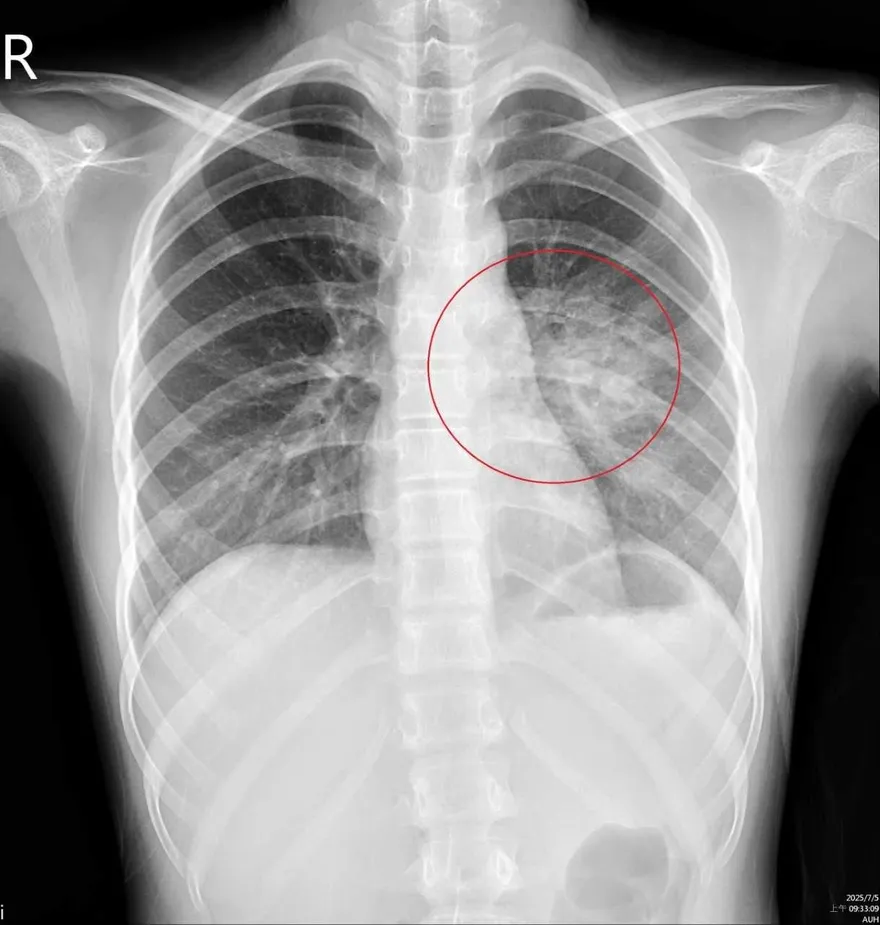

大白肺

嗜睡

咳嗽

全身無力

血氧濃度

肺炎